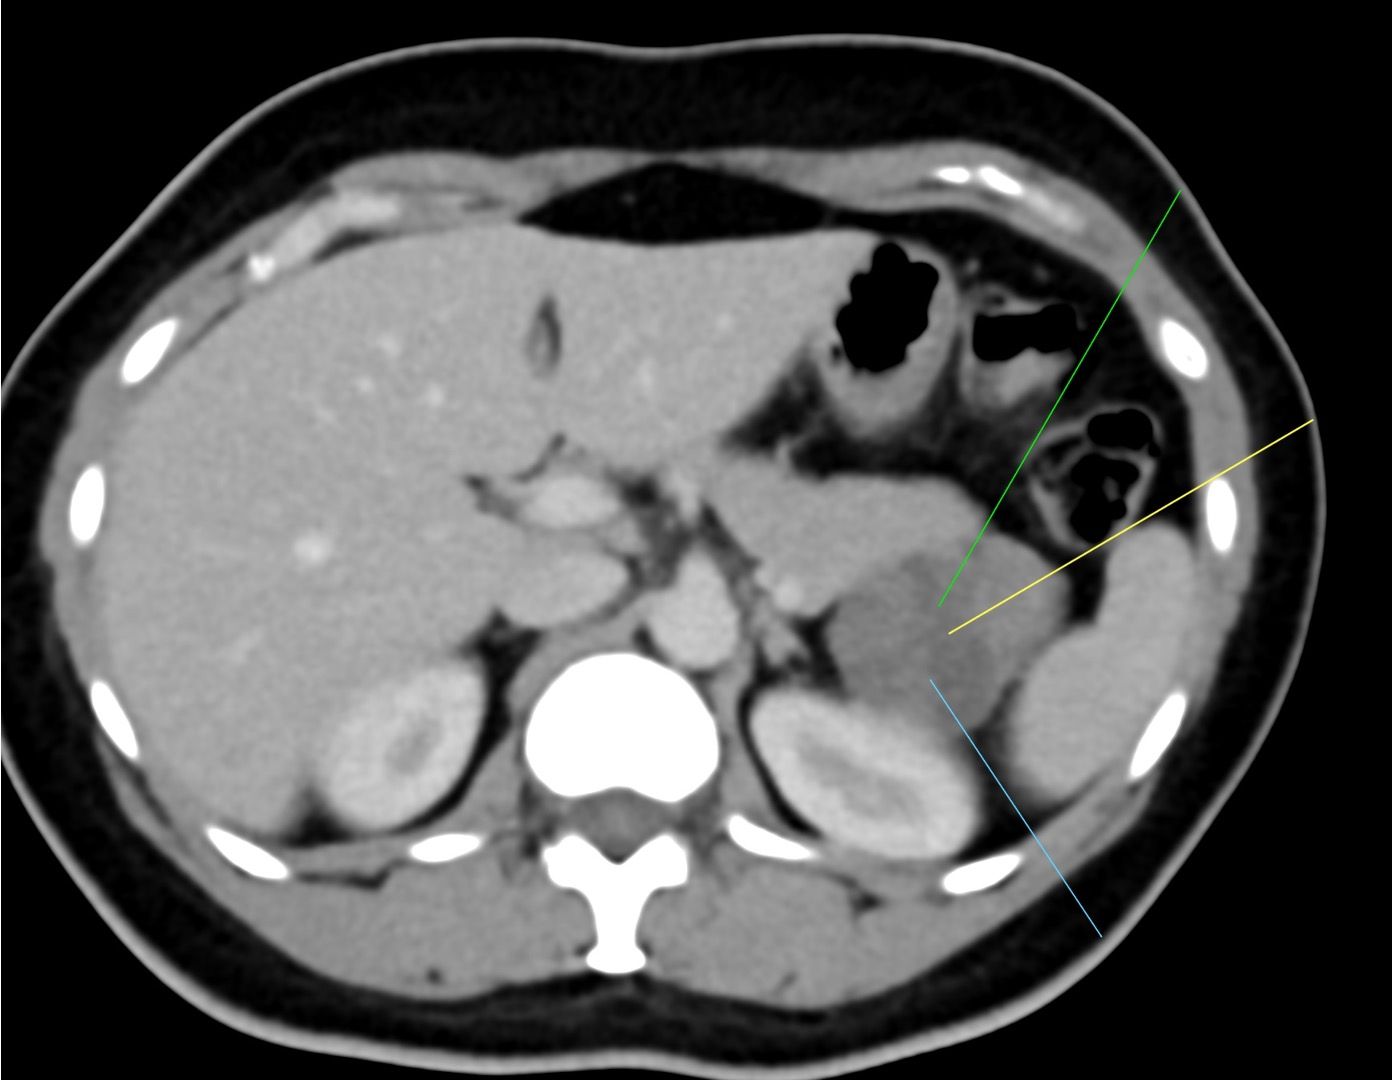

This 45-years old patient presented with a lesion in the tail of the pancreas.

These were the options available for biopsy.